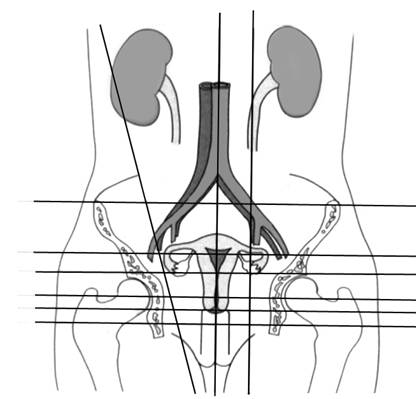

Fig. Nr.341. Sectiune longitudinala prin pelvisul feminin

Fig. Nr. 342. Pelvis feminin vazut dispre peretele abdominal